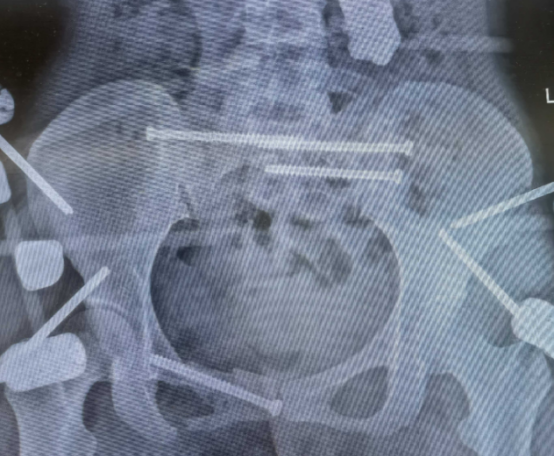

患者的“骶骨骨折”,严重到什么程度?6月19日上午10点半,中心医院东院区的影像检查显示“第1-5骶椎骨折”。

*2025年6月19日患得影像学检查资料刘华水解释说:“患者受伤后骨盆像风吹样,结构十分不稳定。腰下面的骨头叫骶骨,它是人体结构中重要的骨头,由五块骶椎融合而成,构成骨盆的重要部分。骶骨与骨盆起着传导重力和支持、保护盆腔脏器的作用,有很多的软组织附着。骶骨椎体骨折,必须第一时间手术干预,以避免进一步导致盆腔器官和神经功能损伤。”